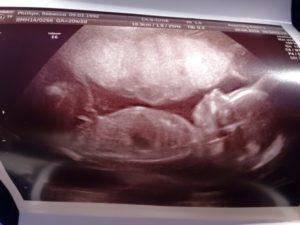

Вторым этапом диагностирования замершей беременности идет УЗИ матки и определение ХГЧ в крови.

В ранних сроках на УЗИ не определяется сердцебиение плода, размеры эмбриона не соответствуют норме или диагностируются анэмбриония (плодные оболочки имеются, а эмбриона нет).

2. УЗИ.

Если при ультразвуковом исследовании диагностирована замершая беременность, видео «показывает» отсутствие сердцебиения у плода.3. Гинекологический осмотр.

- УЗИ, которое, собственно, и покажет остановку биения сердца.